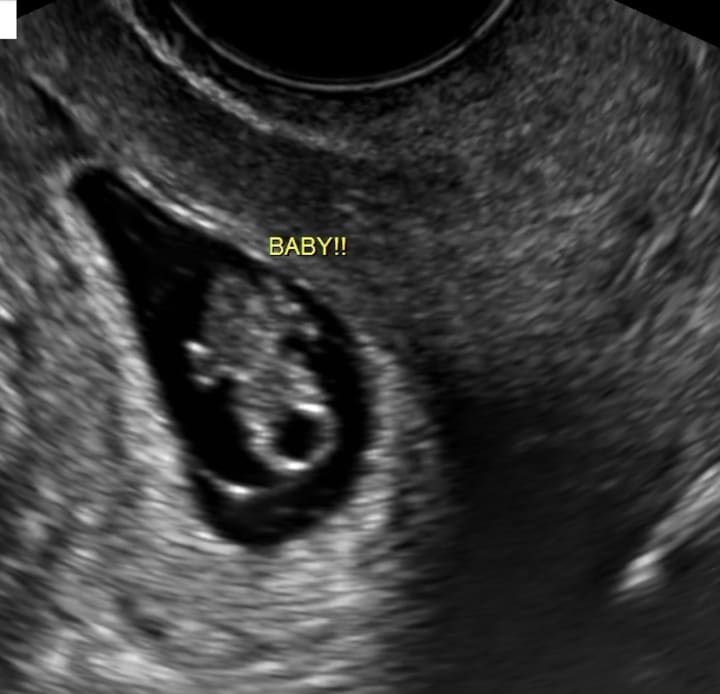

She showed me the images, one with a circle near my ovary, saying, "That's not supposed to be there." But something within me stirred - a fierce need to protect my unborn child. I told my husband, "We're getting a second opinion."

At the next hospital, I repeated my symptoms, and they conducted their tests. It was like déjà vu. But this time, as we waited, my husband reminded me of my dream. The memory was crystal clear, a premonition or a warning? Then came the new diagnosis: they couldn't see anything yet, but there was no cause for alarm - it was normal this early.

Two days later, my HCG levels had soared. The doctors remained unfazed, and I was instructed to return in a week and a half. When I did, they found a yolk sac, nestled safely where it should be, inside my uterus.

Weeks went by, and at my first maternity appointment, anxiety bubbled inside me as I inquired about my ovaries. "Oh, that was just a cyst," the new technician explained, "completely normal." It had resolved on its own, as they often do.